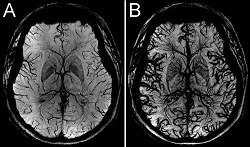

• Drs. GrinsteadRooney, Gahramanov, and Neuwelt are investigating the use of iron-based contrast agents to improve blood vessel conspicuity using susceptibility weighted MRI techniques. The figure at right shows a 7T minimum intensity projection susceptibility weighted images showing human brain vascularity at the level of the basal ganglia (click the image to enlarge). The transverse image of panel A was acquired using inherent contrast from deoxyhemoglobin predominantly from veins. The image of panel B was acquired ten minutes post-Ferumoxytol administration and shows all brain vasculature.